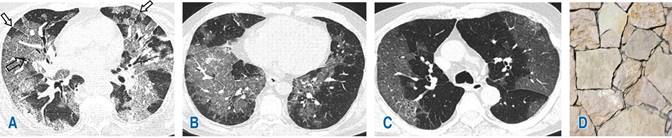

De acuerdo con los hallazgos tomográficos, el patrón predominante en 39% (22) de los casos fue patrón mixto (Figura 1) caracterizado por patrón en vidrio deslustrado, combinado con zonas de consolidación, seguido de patrón empedrado (Figura 2) y patrón en vidrio deslustrado único (Figura 3) con 30% (17) y 29% (16), respectivamente. La localización de las lesiones fue bilateral en 88% (52) de los casos estudiados con mayor involucro de lóbulos inferiores en 55% (31), seguido de afectación en lóbulos superiores en 36% (20). La distribución de las lesiones fue predominantemente subpleural en 48% (27) de los casos estudiados (Figura 4), seguida de afectación con distribución en parches en 20% (11) (Figura 5). En otros hallazgos predominaron las linfadenopatías con 25% (14), seguidas de las atelectasias en 23% (13) (Tabla 2).

Figura 1: Tomografía computarizada de tórax en ventana pulmonar; patrón mixto. A) Vidrio deslustrado bilateral con tendencia a la consolidación en lóbulo inferior derecho (flecha negra). B) En lóbulo medio se identifica área de consolidación (flecha hueca) y parches de vidrio deslustrado en lóbulos inferiores(*). C) Existen zonas de consolidación en lóbulos inferiores asociados a extensa área en vidrio deslustrado (*).